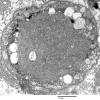

PERIPHERAL NEUROPATHY

4 AXONAL DEGENERATION

3 Electron Microscopy (2)